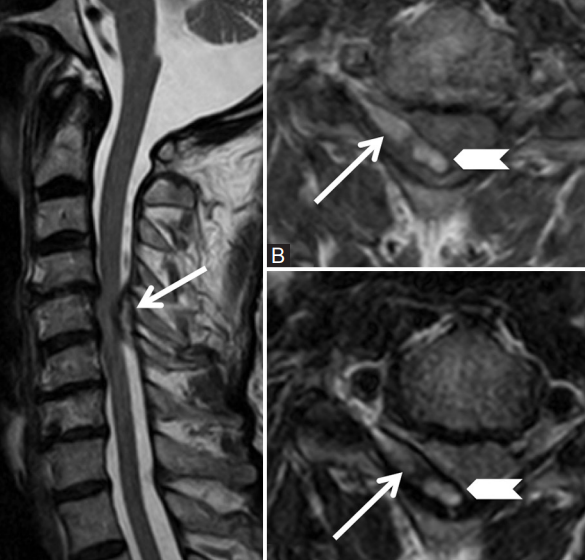

Hématome Epidural

- HyperT1

- Bordures d’hémosidérine

- Le plus souvent sur saignement veineux spontané ⇒ Chez patients anticoagulés

- Autre etiologie: Trauma, iatrogène, MAV

- Symptomatologie brusque (en fonction de la compression de la moelle)